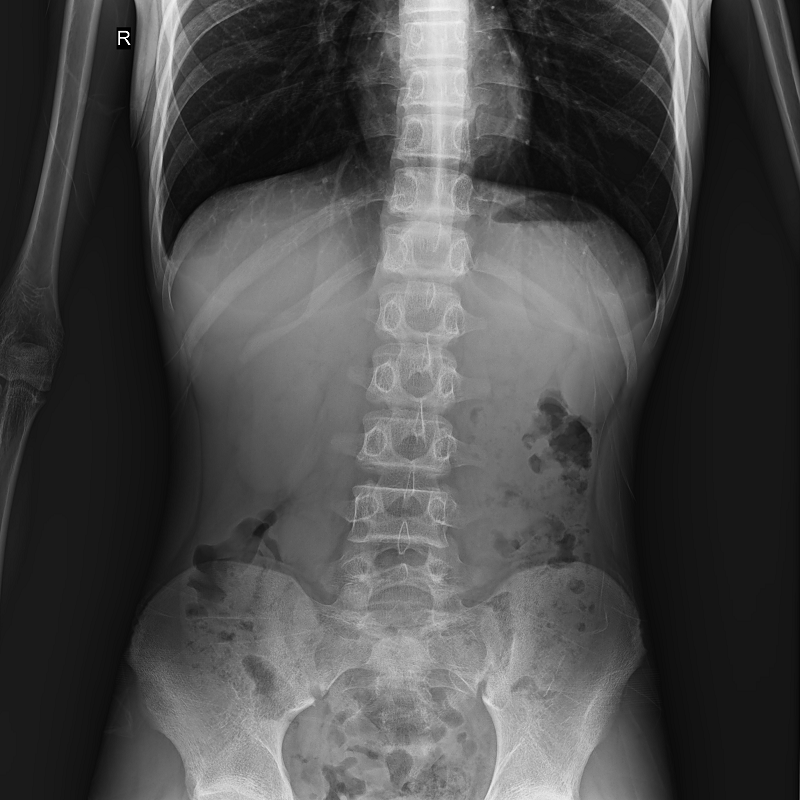

●呈現(xiàn)全下肢或全脊柱圖像

●在脊柱及下肢畸形矯正手術(shù)治療中,為術(shù)前方案制定和術(shù)后復(fù)查提供精準(zhǔn)測(cè)量

●有效解決傳統(tǒng)X光片不能一次成像問(wèn)題,為患者提供更加優(yōu)質(zhì)的醫(yī)療服務(wù)

SID可自動(dòng)拉伸至1.8 米,滿足胸片、職業(yè)性塵肺病檢查等攝影需求

點(diǎn)片裝置可實(shí)現(xiàn)大范圍縱向移動(dòng),高效完成各部位、全身拼接等檢查需求